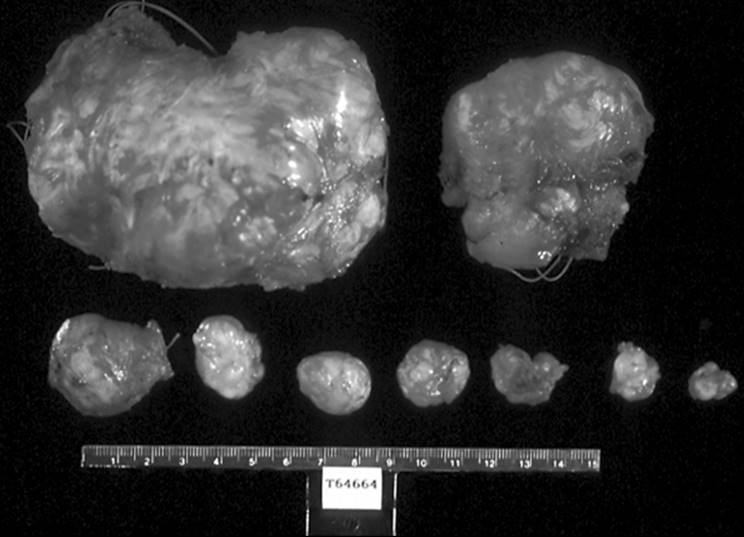

In general, the size, location, or histologic pattern of the myomas have limited predictive ability for recurrence rates. The size of individual myomas may be of greater predictive value, because it appears that extremely large fibroids have a lower recurrence rate after myomectomy than do smaller tumors, despite an overall smaller volume of leiomyomata. It is not clear if the cytogenetic abnormalities have any predictive value for recurrence. The number of leiomyomata may be important in predicting recurrence, with women having single large tumors less likely to have subsequent fibroids detected than women with multiple, particularly smaller diameter, fibroids (Fig. 49.7).

FIG. 49.7. Multiple leiomyomata excised at myomectomy. Many individual fibroids of different sizes and shapes can be encountered within the same patient. Some are very large and obvious, while others may be small and difficult to palpate.